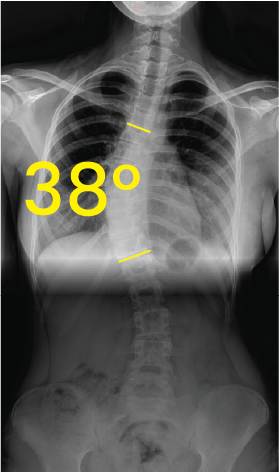

X-ray image of a human torso showing a 48-degree spinal curvature indicative of scoliosis.X-ray image of a spine showing scoliosis with a 38-degree curvature marked between two yellow lines.

Göğüs röntgeninde omurgada 38 derece skolyoz açısını gösteren sarı çizgiler ve 38° rakamı.Göğüs ve lomber omurgada 29 derece skolyoz eğrisi gösteren röntgen görüntüsü.